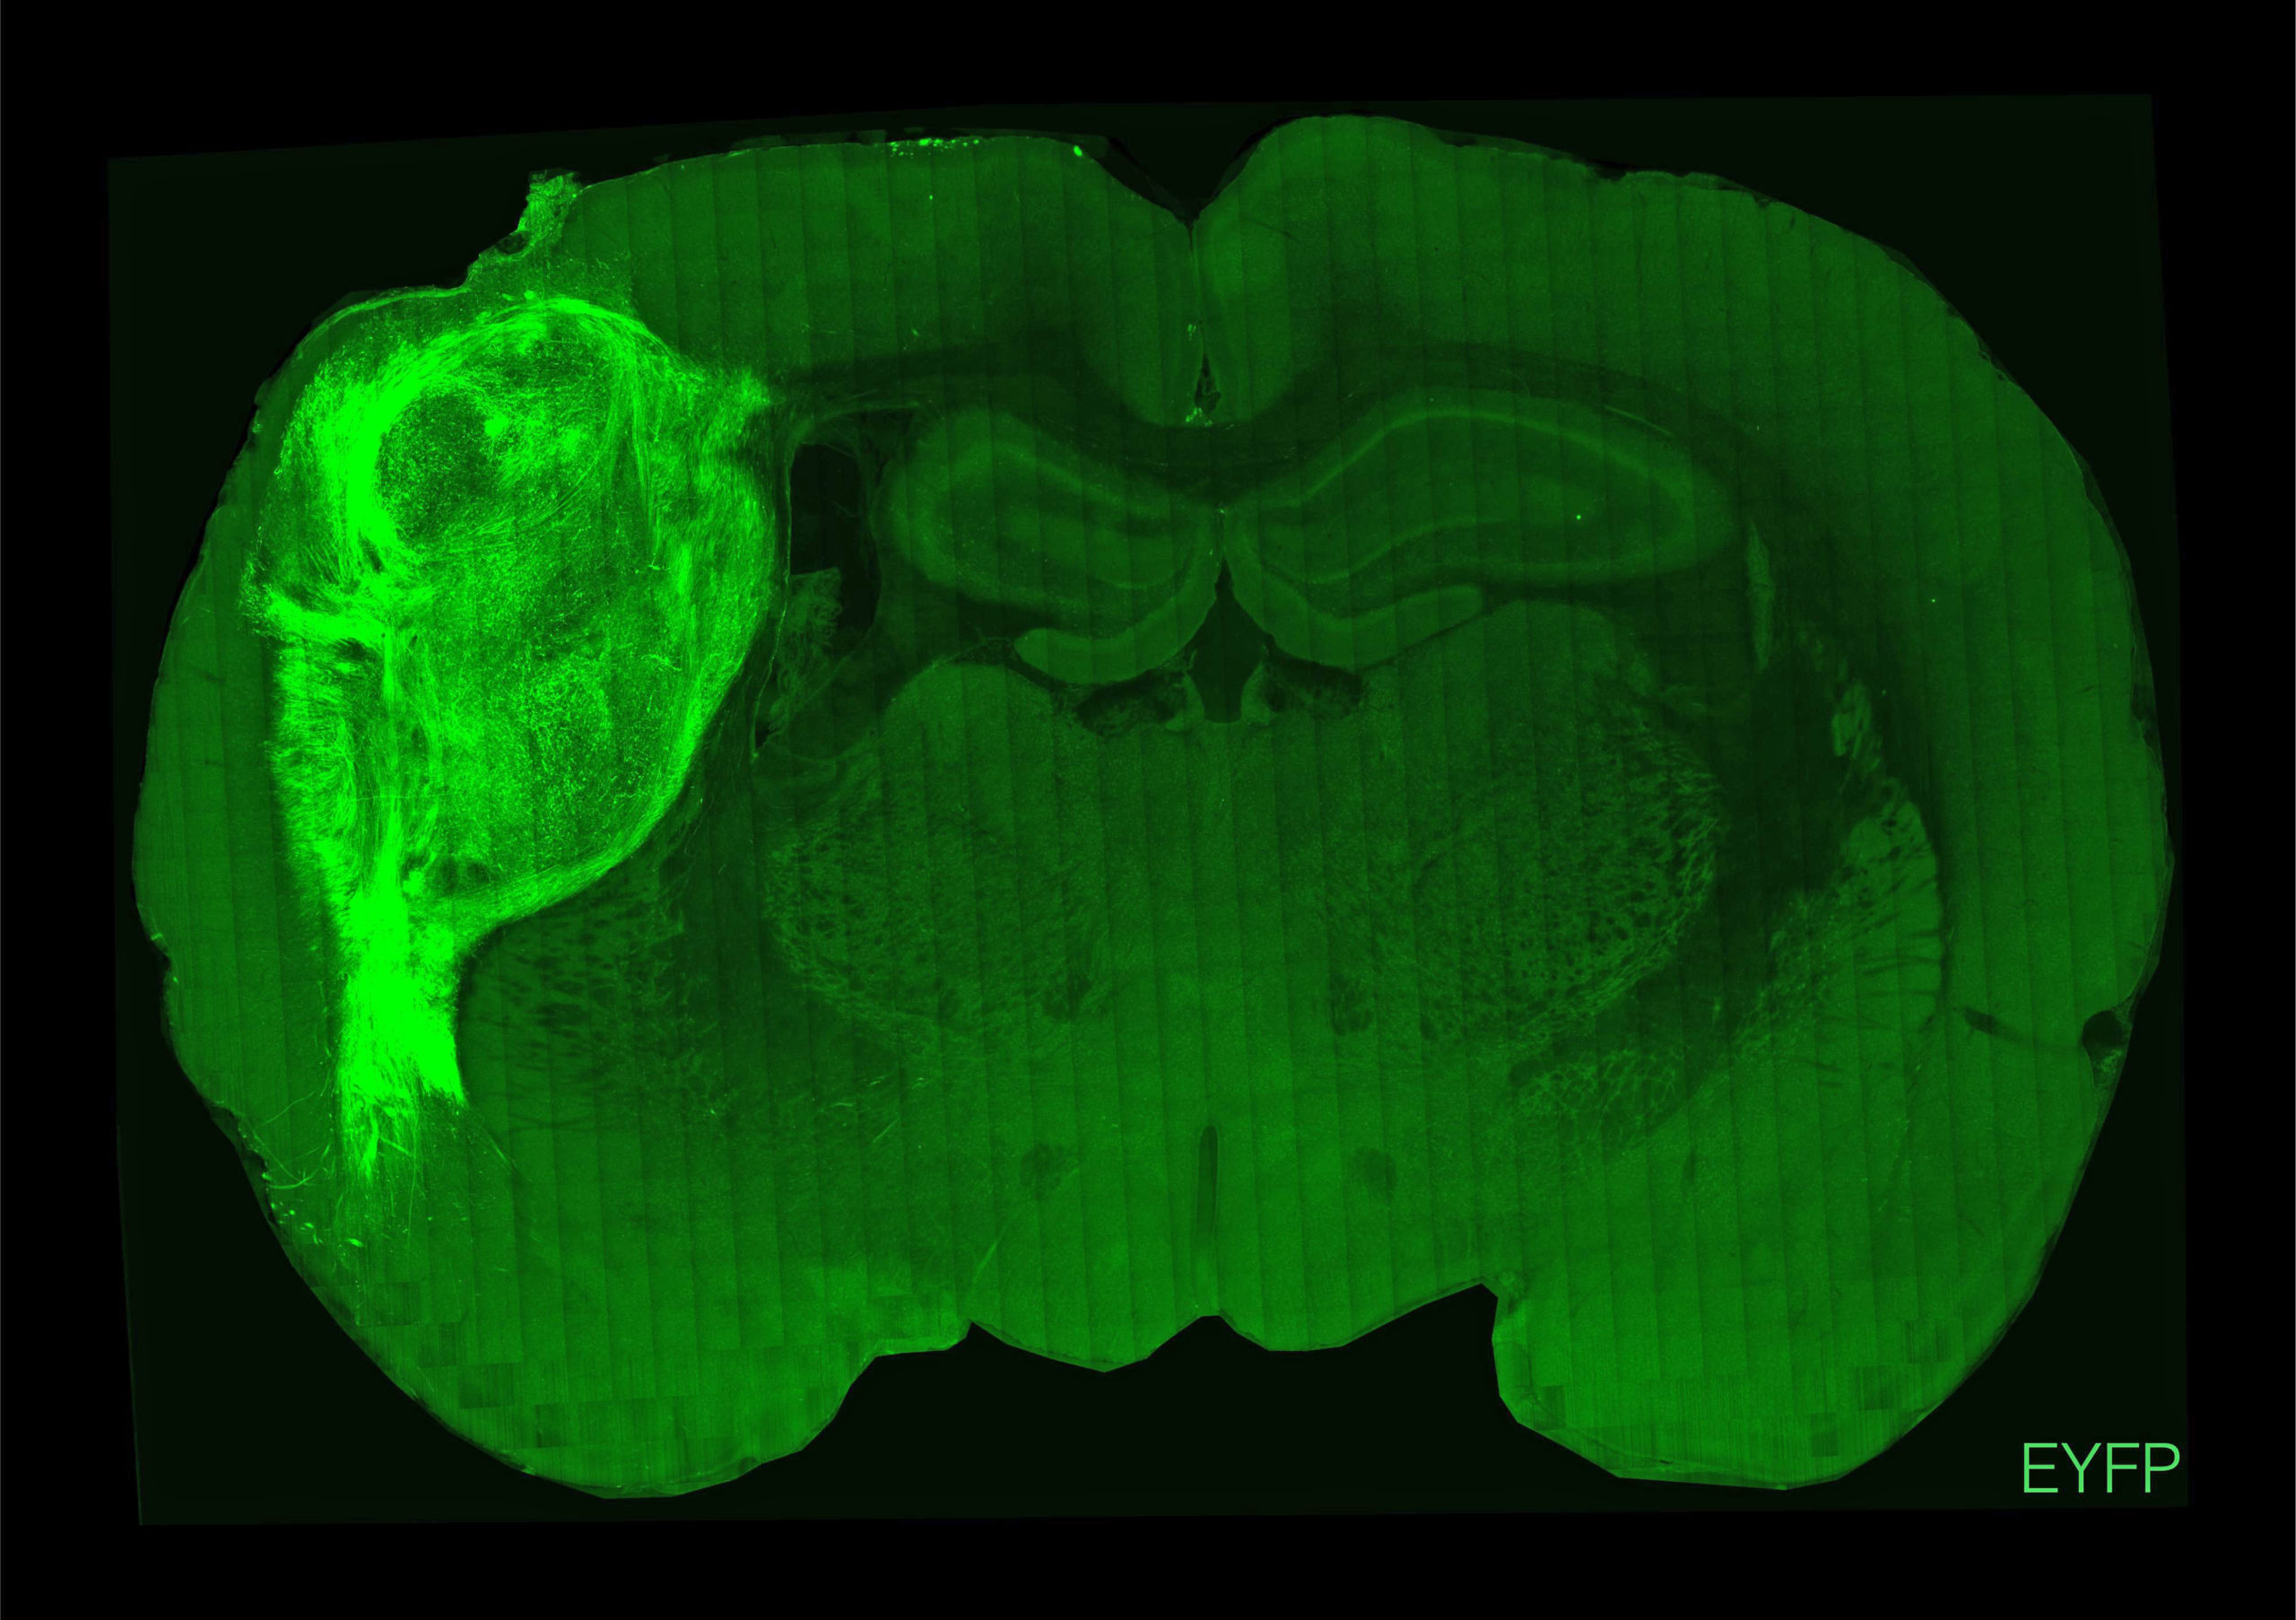

Οι ερευνητές, με επικεφαλής τον καθηγητή ψυχιατρικής και συμπεριφορικών επιστημών Σέρτζιου Πάσκα της Ιατρικής Σχολής του Πανεπιστημίου Στάνφορντ της Καλιφόρνιας, οι οποίοι έκαναν τη σχετική δημοσίευση στο περιοδικό “Nature”, εμφύτευσαν οργανοειδή ανθρώπινου εγκεφάλου (κυτταρικές καλλιέργειες εργαστηρίου που δημιουργούν μίνι-εγκεφάλους) στον σωματοαισθητικό φλοιό του εγκεφάλου 100 νεογέννητων αρουραίων ηλικίας δύο έως τριών ημερών.

Οι εγκέφαλοι των ζώων ενσωμάτωσαν ομαλά το μόσχευμα, το υποστήριξαν με νέα αιμοφόρα αγγεία και το προστάτευσαν με ανοσοκύτταρα. Έτσι οι ανθρώπινοι νευρώνες πολλαπλασιάστηκαν και τελικά κάλυψαν περίπου το ένα τρίτο του ενός ημισφαιρίου του εγκεφάλου των ζώων. Όπως είπε ο Πάσκα, “ήταν σαν να προσθέτεις άλλο ένα τρανζίστορ σε ένα ηλεκτρονικό κύκλωμα”. Τελικά οι ανθρώπινοι νευρώνες σχημάτισαν συνδέσεις (συνάψεις) με τα εγκεφαλικά κυκλώματα των αρουραίων και κατέληξαν να επηρεάζουν τη συμπεριφορά τους, ενώ δεν φάνηκαν κάποιες παρενέργειες στα ζώα.